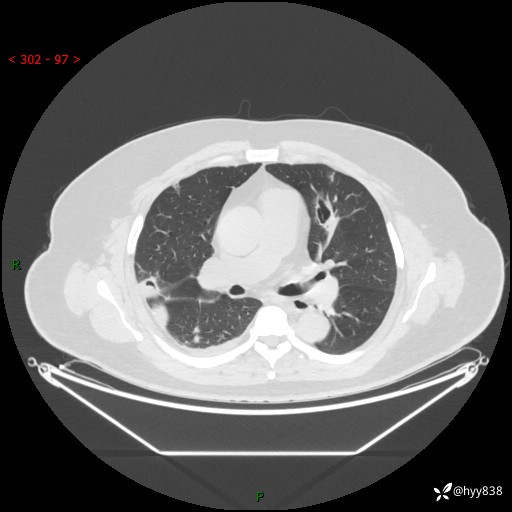

病例中年男性,发热来诊。典型?鉴别疾病谱有哪些,下一步---结果公布~

性别:男

年龄:48岁

简要病史:发热来诊(门诊病人)

胸部CT平扫